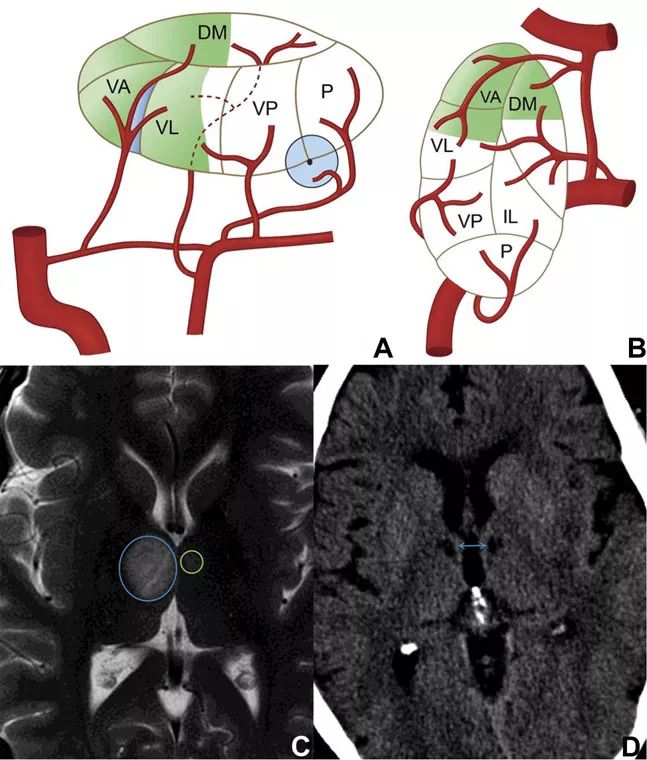

图1 丘脑的供血动脉

图2 丘脑侧视图(A)和背视图(B),示主要丘脑供血动脉及核团

丘脑前部区域由丘脑结节动脉供血,该动脉起源于后交通动脉的中部1/3处,这与源自PCA的其他丘脑动脉区域不同。该部位的梗死临床特征很明显,主要表现为严重和广泛的神经心理缺陷。

该部位梗死早期可表现出不同程度的意识水平改变和沉默寡言,持续的人格变化则见于疾病的后期,包括时间和空间定位障碍、冷漠、缺乏自知力等,情感方面的障碍可能很明显。丘脑前部梗死的其他常见症状是顺行

图3 丘脑结节动脉供血示意图和梗死影像学表现